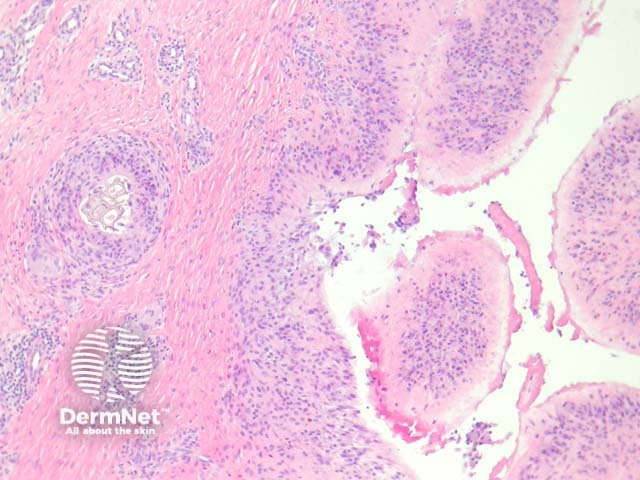

Sections show a irregularly shaped cystic space without an epithelial lining (ie a pseudocyst) surrounded by a dense fibrosis (figure 1). The pseudocyst is lined by a characteristic membrane similar to hyperplastic synovium: the cells of the membrane showed an eosinophilic spindle shaped cytoplasm with processes towards the lumen, which is identical to synovium (figure 2, right hand side; figure 3). It is not uncommon to find foreign material (figure 2, left hand side; figure 4) surrounded by a foreign body reaction and/or synovial metaplasia.

Figure 1

Figure 2